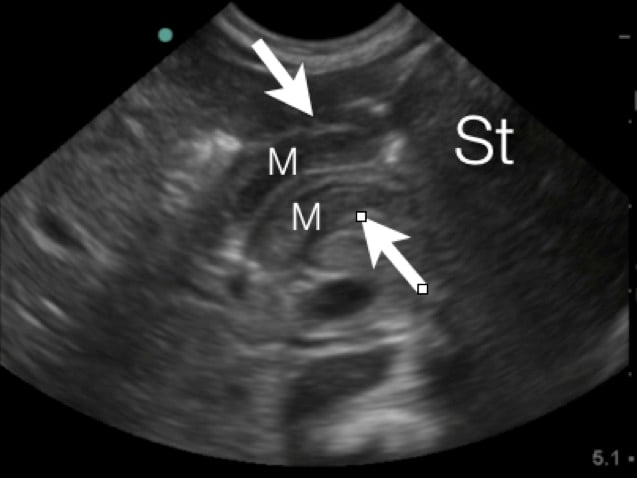

- Figure 4a. Long axis view of the pyloric musle (M) highlighted by white arrows at the distal end of the stomach (St)

- In between the pyloric muscles is the hyperechoic pyloric channel made up of gastric mucosa.

- Figure 4b.Highlighted pyloric channel made up of gastric mucosa